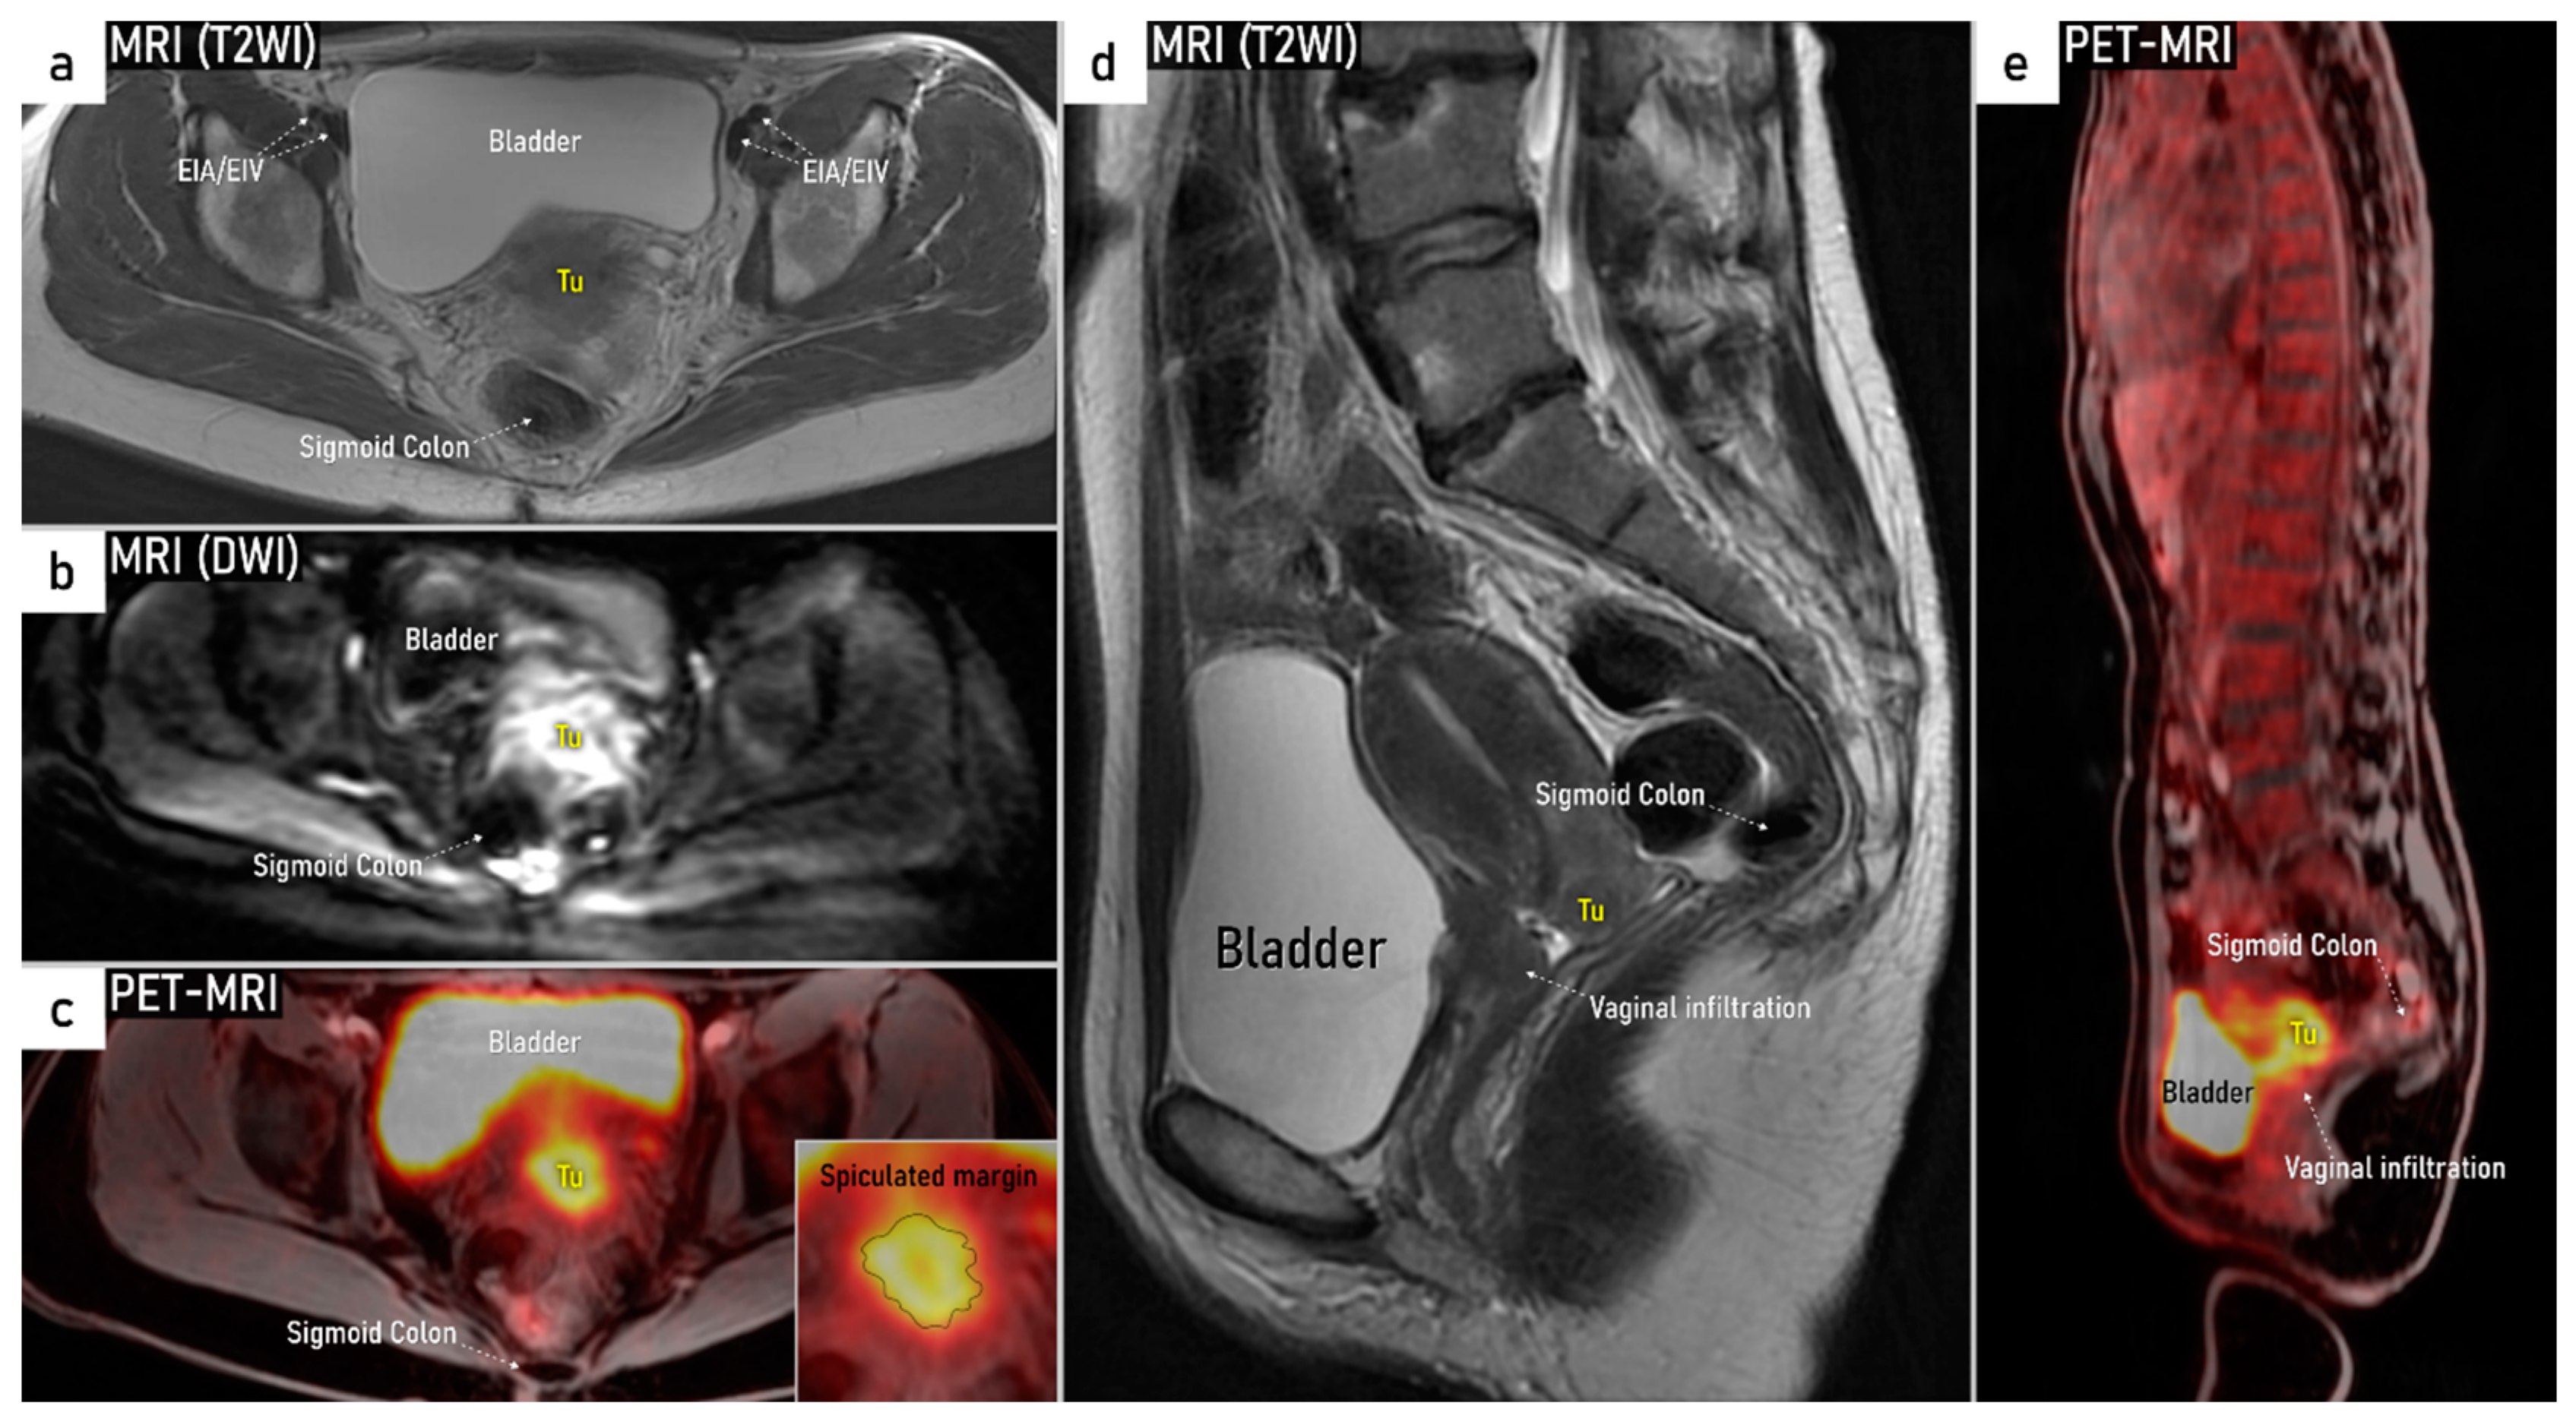

3.3. Extrauterine Extension (Vagina, Parametria, Pelvic Side Wall, Hydronephrosis and Others)

3.4. Extension to Surrounding Organs (Bladder, Rectum, Sigmoid Colon)

| T2b | IIB | Parametrial tumour invasion but no pelvic side wall extension | US: Tumour infiltrates the hyperechogenic pericervical fascia, negative sliding sign, presence of hypoechogenic tumour projections into hyperechogenic parametria. MRI: Tumour disrupts the hypointense peripheral stroma and extends into the parametrium +/− abutting parametrial vessels on T2W images. |

| T3 e | III e | Carcinoma involves the lower third of the vagina and/or extends to the pelvic side wall and/or causes hydronephrosis or non-functioning kidney | Tumour infiltration of the lower third of vagina or lateral pelvic side wall by US or MRI. Pelvic side wall infiltration is considered when the tumour causes hydroureter, infiltrates the obturator internus, piriformis, and levator ani muscles, encases the iliac vessels, or invades the pelvic bones on US or MRI. |

| T4 f | IVA f | Tumour invasion into the mucosa of the bladder or rectum (biopsy-proven) or into adjacent organs. | Tumour invasion into the mucosa of the bladder or rectum on imaging, confirmed by biopsy. US: Negative sliding sign, hypoechogenic tumour infiltration of bladder/rectal wall up to echogenic mucosa with polypoid tumour seen intraluminally. MRI: Focal or diffuse disruption of the normal T2-low signal intensity wall of the bladder/rectum, irregular or nodular wall, sometimes including an intraluminal tumour mass. Bulous edema sign, which is hyperintense thickening of the bladder mucosa on T2W images, is only an indirect sign of invasion and should not be regarded as T4 unless confirmed mucosal infiltration at cystoscopy. Infiltration of the posterior bladder wall without mucosal infiltration should not be regarded as T4a. |